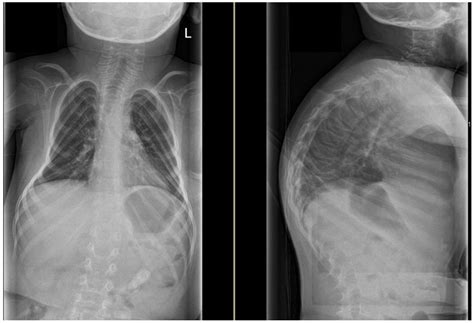

Comprehensive Solutions For The Correction Of Spinal Deformities

Modern Management of Spinal Deformities | 9783132431867 | Thieme Webshop